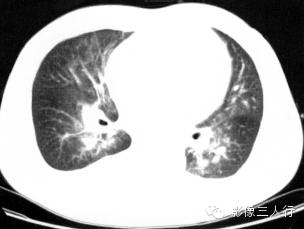

【报告范例2】

报告书写:胸廓对称,两肺下叶磨玻璃密度和肺实变影像,双侧对称,呈“蝶翼征”。双侧肺门不大,纵隔居中,其内未见肿大的淋巴结。心脏大小正常,胸壁软组织未见异常(图2)。

图2肺泡性肺水肿